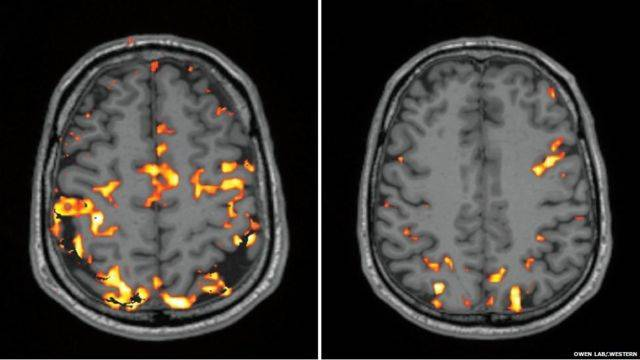

Мозг начинает замечать нехватку отдыха. Замедляется работа лобных долей — а это значит, что логически мыслить и быстро принимать решения становится труднее.

На снимке, который сделан после бессонной ночи, видно, что особенно снижена активность во фронтальной и теменной долях, которые, как известно, отвечают за принятие решений и память.